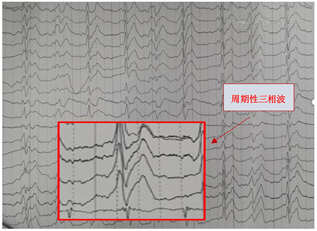

辅助检查脑脊液中14-3-3蛋白阳性,脑电图呈现有"周期性三相波";头颅核磁DWI显示有大脑皮质呈典型"花边征"。结合患者临床特征,根据WHO诊断标准,考虑诊断可能为克-雅病。

入院第6天查体较前变化体征为:双上肢肌张力略增高,双侧指鼻试验、轮替试验、跟膝胫试验等共济运动欠灵活,步态不稳,需搀扶,双侧腱反射对称(+++),双侧踝阵挛(+),双侧Babinski’s征(-),脑膜刺激征(-),余查体同前。入院第6d精神检查:神志淡漠,表情呆愣,多数时间下为亚木僵状态,对问话较前有反应,张口说话困难,反复提问下可回答几个字,对一些医生的交谈可以有笑容、自嘲的表现,对大多数交谈内容反应不明确;对命令要求可有反应,但难以配合;可疑认知功能减退(患者对检查欠配合),双手姿势怪异,无自知力。2020年12月15日头颅MRI示右侧额颞顶枕叶、左侧额叶、右侧尾状核头可见DWI高信号(图1)。于2020年12月15日转诊至外院神经内科就诊。

本例患者脑电图呈现有"周期性三相波",脑脊液中14-3-3蛋白阳性,头颅核磁影DWI显示有大脑皮质呈典型"花边征"及结合患者快速进展的临床症状考虑很可能为克雅氏病即Creutzfeldt-Jakob病(CJD)。

最后CJD典型辅助检查表现出现在不同的疾病时期,对临床甄别本病造成了一定困难。目前,CJD的确诊需要在死后或活检获得的脑组织中检测异常折叠的、CJD特异性蛋白酶耐药朊蛋白(PrPCJD),由于组织活检有感染病毒风险且活检程序繁琐、具有创伤性,因此,临床上对CJD的诊断往往具有挑战性。临床医生可以通过无创检查即脑MRI扫描、脑电图和脑脊液检查来协助诊断。头颅MRI:最早变化可出现在发病后1个月,并发生于脑电图及脑脊液出现异常结果之前;其敏感度及特异度可达到100%[1],少数患者早期可无异常改变。MRI的DWI相上可见对称或不对称性皮质"缎带征"或"花边征",基底节区(尾状核、壳核、丘脑枕)高信号对CJD早期诊断具重要意义[12]。FLAIR图像上双侧丘脑枕及丘脑背内侧的异常高信号为"丘脑枕征"和"曲棍球征"[1,5]。脑电图的早期敏感性一般但特异性较高,脑电图早期主要表现为非特异性弥漫性慢波及额部节律性6活动,中期则出现特征性的周期性尖慢复合波(为CJD标志性改变),至晚期则再次呈现非典型特征表现为类似昏迷状态的慢波及低电压活动[13]。本例患者在我院住院期间因配合度差未完成脑电图,故减少了诊断参考依据。最后对于脑脊液检查方面,随着病情进展,脑脊液蛋白数增加,目前唯一纳入WHO诊断标准中的分子蛋白是脑脊液中14-3-3蛋白。利用免疫方法检测脑脊液中14-3-3蛋白,在一定范围内该蛋白增加与患者典型临床表现增加呈正相关[14]。